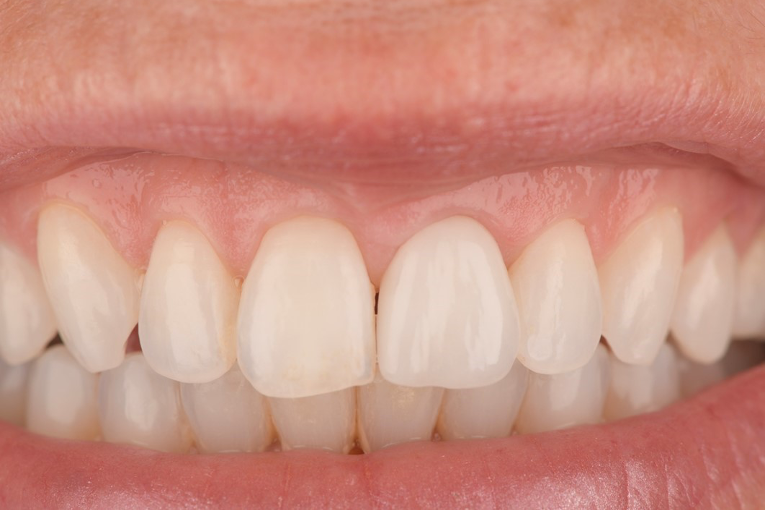

An example of one of the first cases that we did this way is below, including the most recent images of the case.

This illustrates the power of guided surgery and constant improvement.